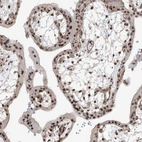

Immunohistochemical staining of human Placenta shows strong nuclear positivity in trophoblastic cells.